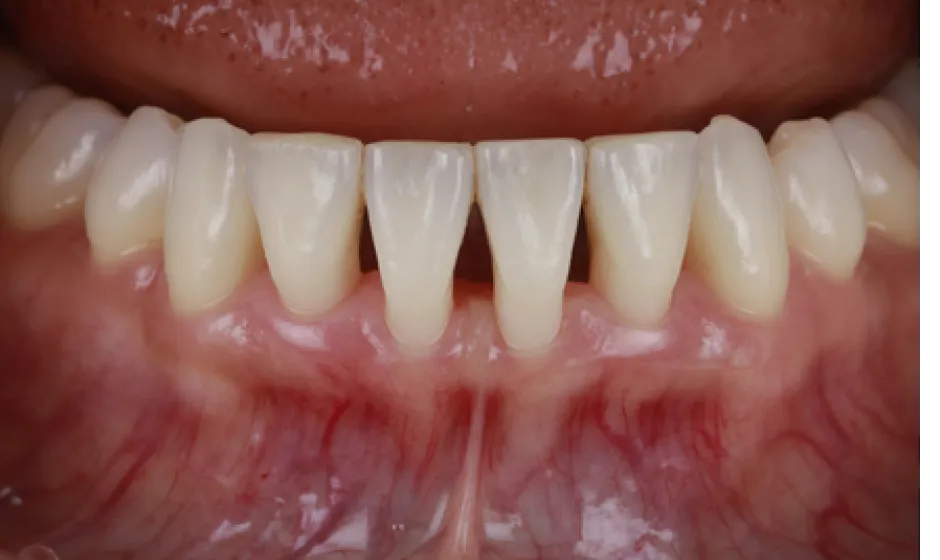

02歯周病・

重度歯周病治療歯周病は痛みが少ないまま進行し、気づいた時には歯がグラつく、膿が出る、噛みにくいといった状態になりやすい病気です。けれど、重度でも「もう無理」と決めつける前に、歯ぐき・骨・噛み合わせの状態を丁寧に評価し、今できることを一つずつ積み上げれば、守れる歯はあります。

当院では検査に基づき、基本治療から必要に応じた外科的治療や再生療法の検討まで、長期維持を見据えて段階的に進めます。津市で歯周病を本気で治したい方に、寄り添える歯科医院でありたいと考えています。症例1

症例2

- 治療名

- 【高度審美形成】歯間乳頭再建術

- 患者様

- 40代女性

- 執刀医

- Dr. 大杉

- 治療期間

- 約1年

- 治療費

- 300,000円(税込)

- リスク

- 移植組織の定着後も、メンテナンスが予後を大きく左右します。

特に歯間ブラシの不適切な使用や過度なブラッシング圧は組織の退縮を招くため、術後は当院の指導に基づいた厳密なプラークコントロールが必要です。